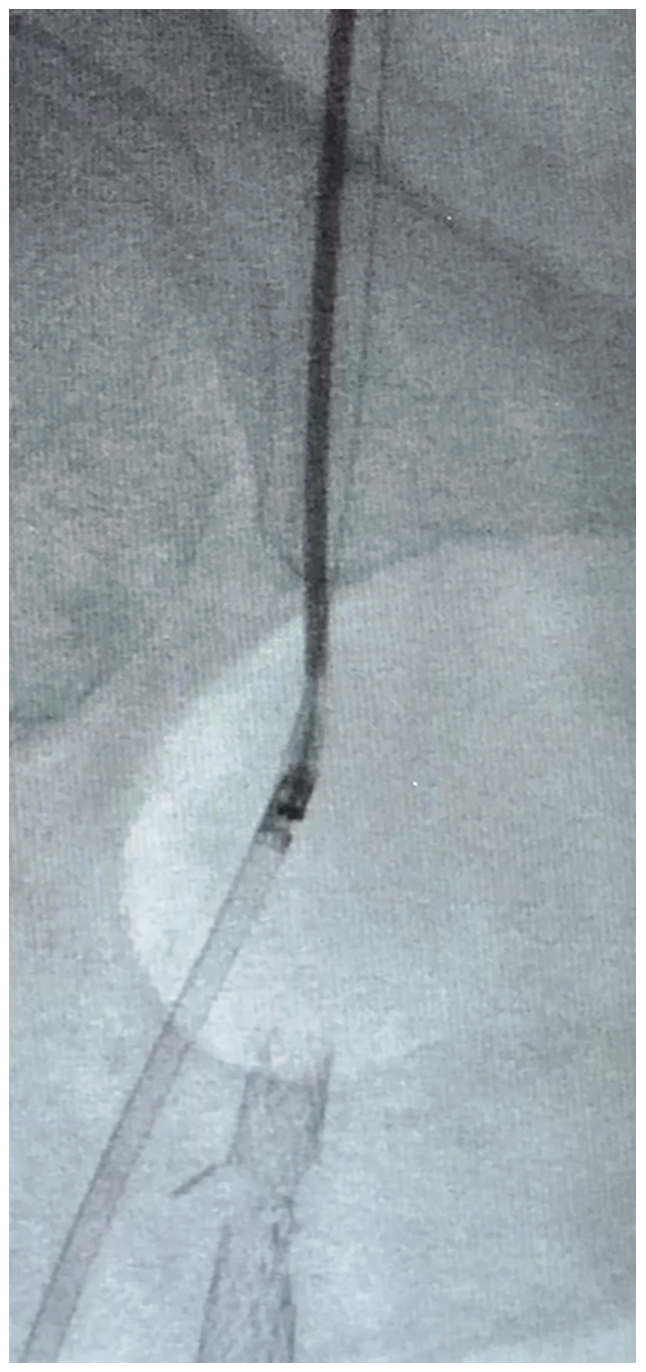

To execute this strategy, a 7 French, 45 cm sheath was placed over the aortic bifurcation and positioned in the very proximal common femoral artery. The patient was anticoagulated with heparin 80 units/kg intravenously. A 6 mm SpiderFX embolic protection device (EPD) (Medtronic) was placed in the largest first-order branch of the PFA and a magnified road map of the lesion was created at 25 degrees right anterior oblique (RAO). A HawkOne LS directional atherectomy device (Medtronic) was selected for its larger plaque excision capability and its shorter nose cone, given the short length of the lesion, and a desire to keep the EPD closer to the lesion and thereby protect more branches (Figure 3). A series of six initial passes with the device at 1-2mm per second was made in a uniform, radial manner. Subsequent angiography demonstrated a marked reduction in stenosis and an additional 5-6 passes were made in a targeted fashion at remaining locations of visible disease. With less than 30% stenosis remaining, an In.Pact DCB (6 mm x 40 mm) (Medtronic) was selected based upon IVUS measurements and inflated to nominal pressure for three minutes (Figures 4-5). Follow-up angiography demonstrated <20% residual stenosis with no evidence of dissection or distal embolization (Figure 6). These findings were confirmed by final IVUS imaging and the procedure was completed without complication (Figure 2B). The arteriotomy was closed by Perclose (Abbott Vascular) and the patient was ambulatory two hours after the procedure. Dual antiplatelet therapy was prescribed for three months following the procedure and low-dose aspirin indefinitely.

approximately 12 passes of the device.